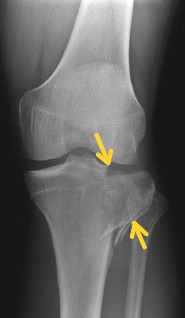

Röntgenbild einer schwerwiegenden Arthrose im Kniegelenk mit nahezu aufgebrauchten Gelenkspalt innen- und außenseitig (Pangonarthrose)

| Grad 4 | Schwere Arthrose | Vollständiger Knorpelverlust | Ruhe- und Nachtschmerz, starke Funktionseinschränkung | “Knochen auf Knochen”, ausgeprägte Deformierung |